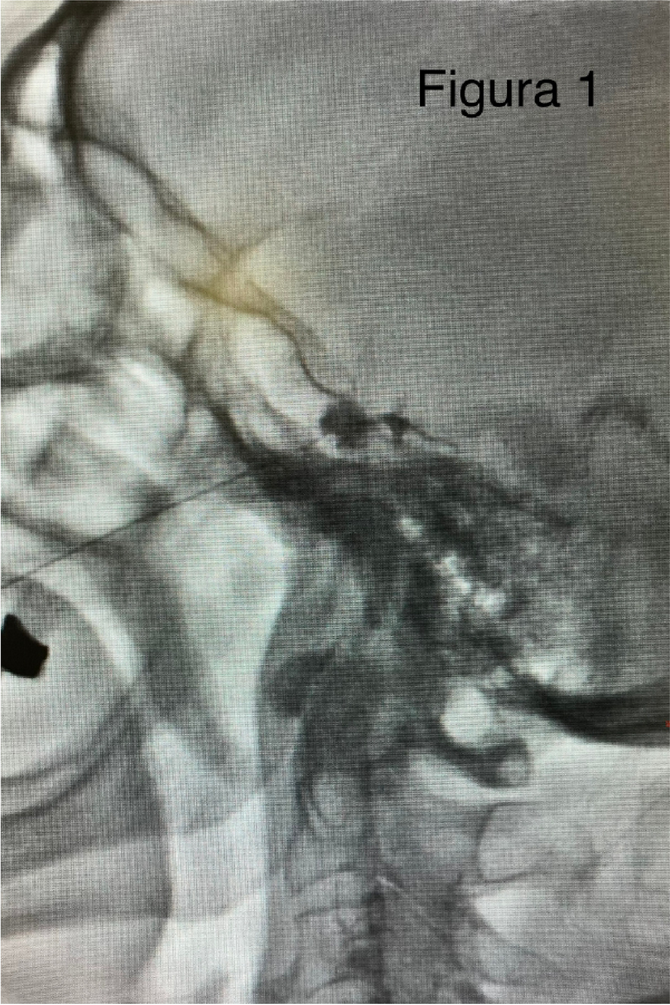

A few hours after the admission in ICU he reported a blunt abdominal pain, mainly on the right side, nausea and the exams showed increased amylase levels, urologists excluded any surgical involvement of pancreatic tissue and suspected a transient sphincter of Oddi dysfunction [3]. After one night in ICU he was transferred to the urology ward due to his clinical stability, even though Amylase peaked at 2340 U/l. Two days later abdominal pain increased to severe, with characteristics of peritonism and increased inflammatory markers. An abdomen-thorax CT scan revealed acute pancreatitis (AP) (Figure 1) and he was transferred to ICU. He started a standard treatment for acute pancreatitis and antibiotic therapy [4].

On postoperative day nine, due to general deterioration of clinical conditions and further anemization that required blood transfusion, he underwent an emergency laparotomy, in which propofol was not used as an anesthetic drug, that found a completely necrotic pancreas. The following day he faced a multi organ failure (MOF) which rapidly led to death. Consent to publish the case report was accorded by the family.

Acute pancreatitis (AP) Is a complex and severe disease with a high mortality rate [4]. Propofol, is a common anesthetic drug which is widely used in daily practice for sedations and general anesthesia [5], few cases of Propofol Induced AP have been published, in which the diagnosis has been made excluding more common causes [6].

In fact, Propofol is listed as a possible cause of AP, class Ib, based on the classification of Badalov et al. [7]. Following the scheme proposed by the systematic review by Haffar et al for Propofol induced AP [6] we could confirm that our hypothesis is plausible. He satisfied the American College of Gastroenterology criteria for AP [8,9] and it is classified as severe acute pancreatitis according to the Revised Atlanta Classification with peripancreatic necrotic fluid collection [10]. Marshall score [11] after admission was two and Naranjo et al [12] probability scale for drug adverse reaction was three, meaning that the adverse reaction is possible. Latence according to Badalov et al [7] has been short or intermediate. Exclusion of other plausible causes, timing of pancreatitis symptoms and previous cases in literature support our hypothesis of propofol induced pancreatitis.